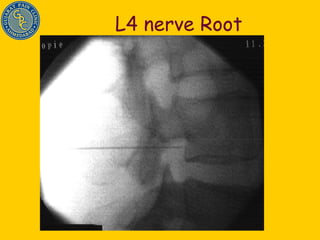

L4 nerve Root